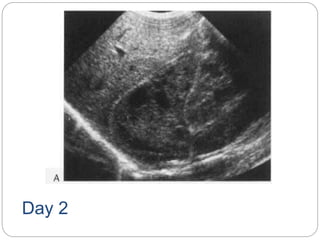

 Ultrasound in the first few days of life

usually demonstrates an avascular

heterogenous adrenal mass that

becomes cystic and smaller over the

following weeks as clot retraction occurs

Day 2

Resolving adrenal heamorrhage commonest cause of an adrenal mass  Associated with perinatal stress, hypoxia, septicaemia and hypotension  may be unilateral or bilateral  Adrenal insufficiency is rare, even in bilateral cases.  Ultrasound in the first few days of life usually demonstrates an avascular heterogenous adrenal mass that becomes cystic and smaller over the following weeks as clot retraction occurs